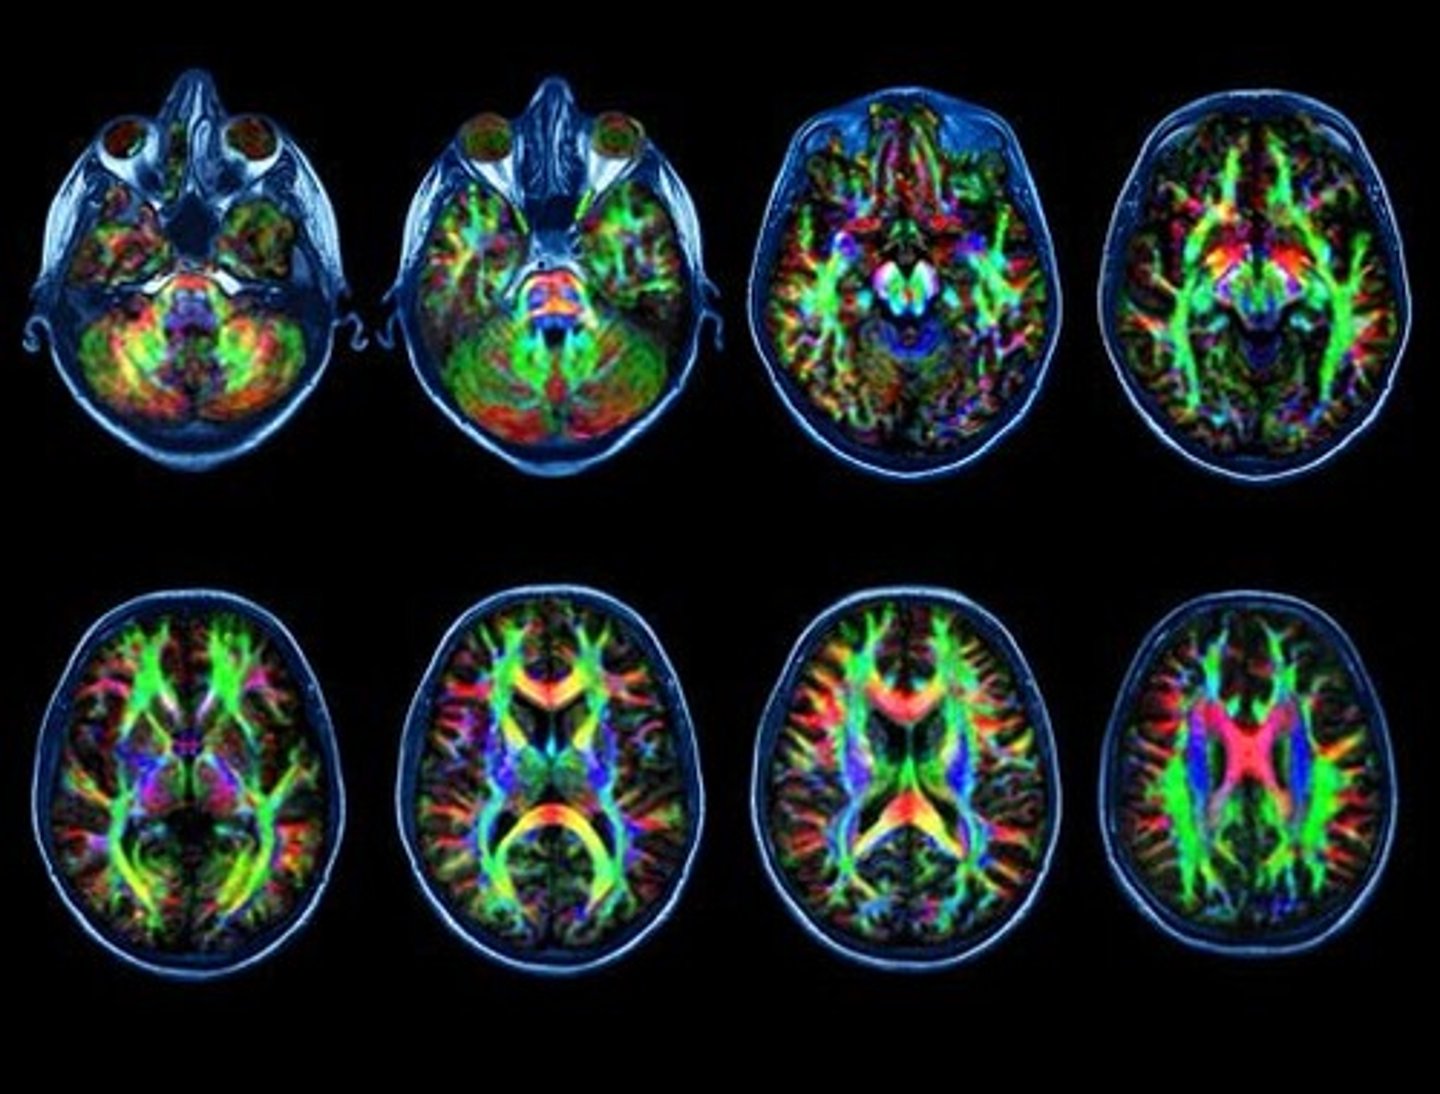

DTI

What type of scan is this?

<p>What type of scan is this?</p>